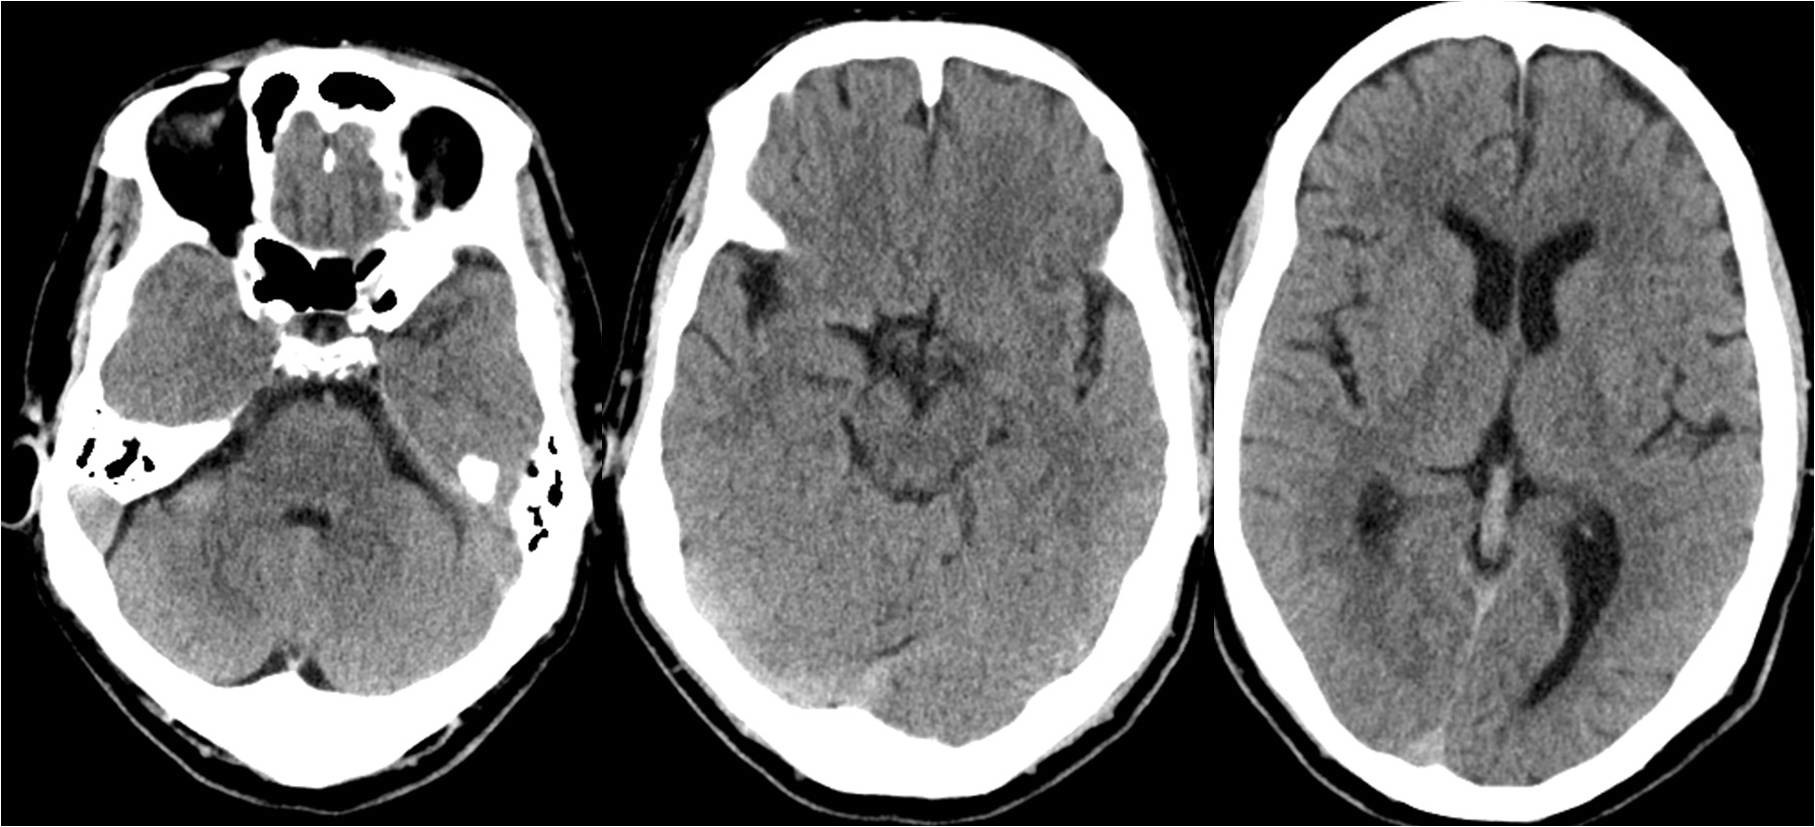

患者突发头痛头晕4小时入院,头ct示蛛网膜下腔出血.